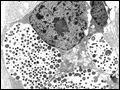

| Figure 176-1 Chlamydial intracellular inclusions filled with smaller dense elementary bodies and larger reticulate bodies. [Reprinted with permission from WE Stamm: Chlamydial infections, in Harrison's Principles of Internal Medicine, 17th ed, AS Fauci et al (eds). New York, McGraw-Hill, 2008, p... | |